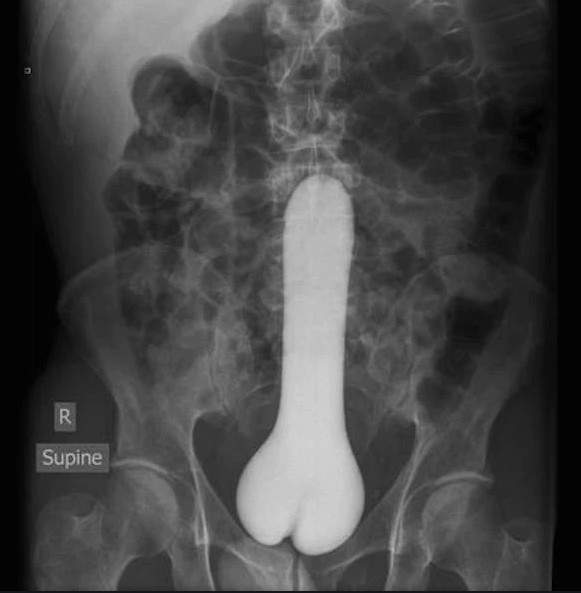

我剛剛說試著PS不是我自己塞東西,然後去照X光下來P成圖片喔...

Σ>―(〃°ω°〃)♡→異物突入X光照 閱覽注意級請勿在家模仿喔